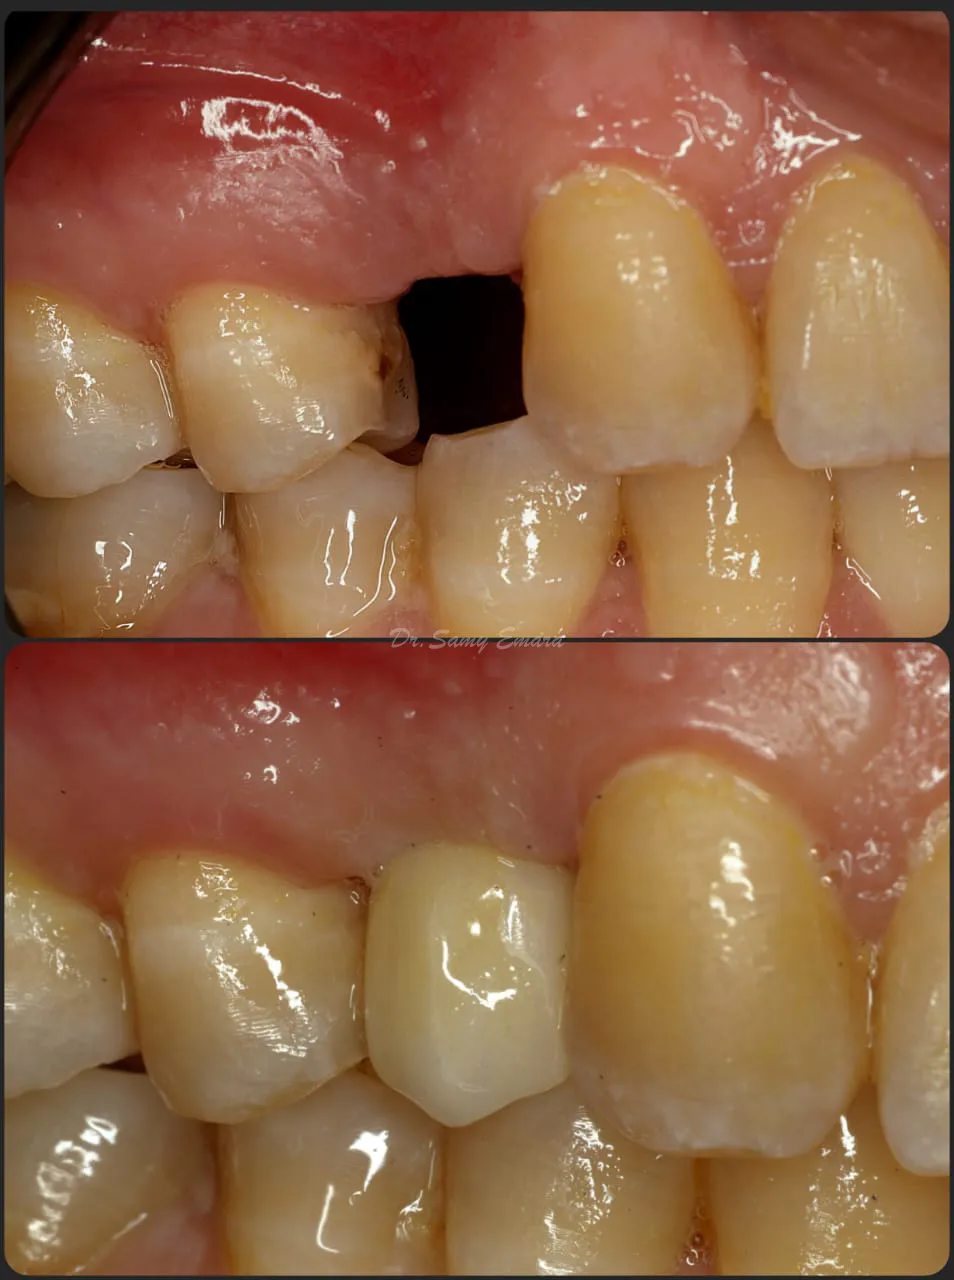

Implant